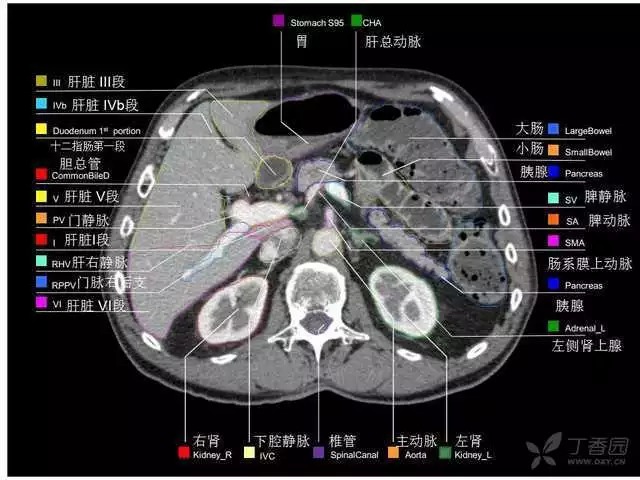

腹部肝脏高清CT断层的图谱

全腹部高清CT图谱,淋巴结彩色图谱,血管解剖图谱大汇总!

肝段,肝内管道的分布规律